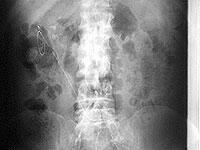

写真7は 72 歳、女性、糖尿病で卵巣腫瘍切除術後、胆摘後。

下行結腸と壁側腹膜の間の溝にカテーテル先端が固定されています。

普段、横になっていることが多いとこの位置にカテーテル先端が移動しますが、左下側臥位でバッグ交換すると注排液の異常は生じません。

写真8は上腹部へカテーテルが移動したときに長時間排液して大網がカテーテルにはまり込み腸管の動きでカテーテルが引き伸ばされています。

注排液ができなくなったためカテーテル交換をおこないました。